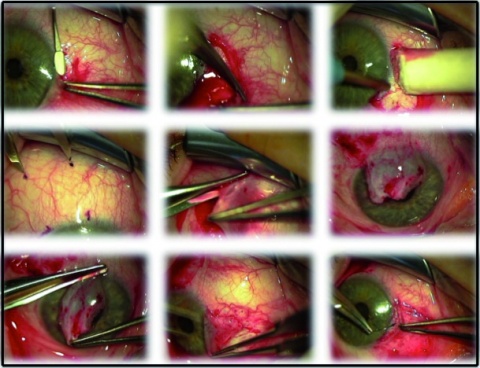

Technik (a) Pterygiumlokalisation; (b) Pterygiumexzision; (c) Defekt

(schwarz schraffiert)

(d) Präparieren eines Bindehaut-Limbus-Transplantates von temporal oben (weiß);

(e) Deckung des Defektes mit Transplantat so, dass der limbusnahe Anteil auch wieder limbusnah zum Liegen kommt und Adaption.

Im klinischen Alltag werden heute zur chirurgischen Behandlung des Pterygiums vorrangig die Bare-Sklera-Technik in Kombination mit einer Defektdeckung mittels freiem Bindehaut- bzw. freiem Bindehaut-Limbus-Transplantat (Abb. 2 und Abb. 3) angewandt. Gegebenenfalls kann zusätzliche eine intraoperative Applikation von Mitomycin C 0,02 % erfolgen. Zudem wird die Adaption des Transplantates mit Fibrinkleber statt mit Nähten diskutiert [34, 13, 26, 31].

Abb. 1 und 3: Universitätsaugenklinik der Paracelsus Medizinischen Privatuniversität Salzburg – Archiv Augenheilkunde, eigene Patienten